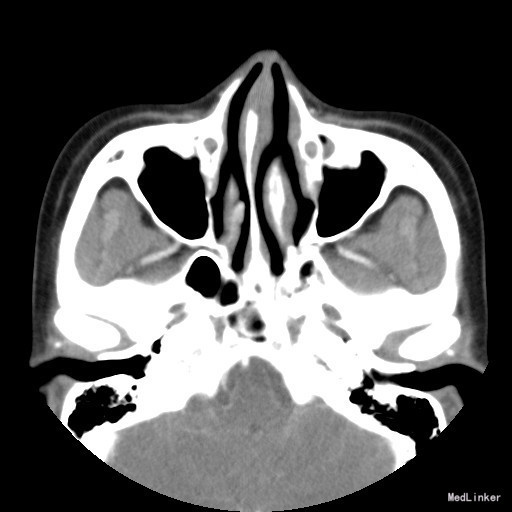

诊断:鼻腔血管瘤 治疗:入院后鼻窦CT示:右侧中鼻甲血管瘤,排除手术禁忌症,于局麻+表麻下手术,术后病理提示:(右侧鼻腔血管瘤)结合临床,可符合血管瘤。